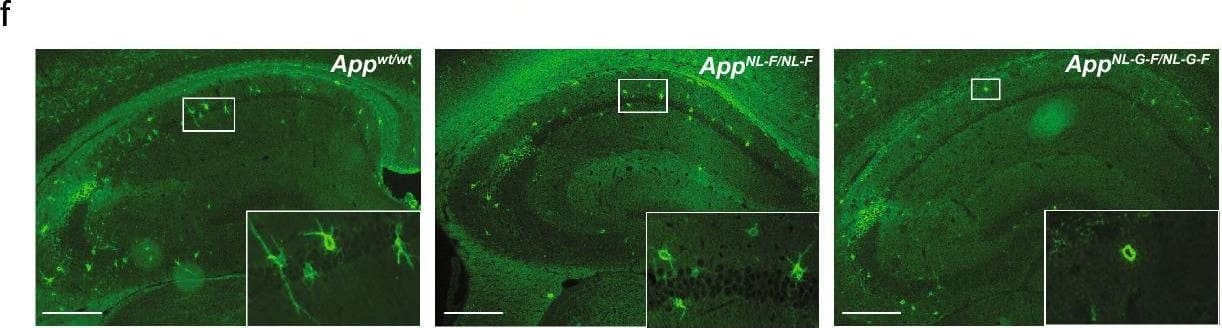

Detection of Mouse Decorin by Immunohistochemistry Increased CSF-decorin in three different mouse models of A beta pathology. a, b Immunostaining and quantification of decorin in the ChP. Scale bars, 100 µm. (n = 4). c Double immunostaining of DCN and PV or d SRIF in mouse hippocampus. e Quantification of decorin-positive cell-type distribution. Scale bars, 500 µm. (n = 3). f, g Immunostaining and quantification of decorin in the hippocampus. Scale bars, 500 µm. (n = 4). h Mouse CSF-decorin levels in three months old (n = 5), i 13 months old (n = 4–5), j 18 months old (n = 3–5) mice were measured by ELISA and quantified. k CSF-decorin levels in AppNL-F/NL-F mice of different ages were measured and quantified. (n = 3–5). l Decorin levels in A beta 42 treated mouse primary neurons and (m) were quantified (n = 4). n Quantification of decorin levels in conditioned media. (n = 8). Data in (b, g–k) were analyzed by one-way ANOVA followed by Dunnett’s multiple comparisons test. Data in (m, n) were analyzed by student’s t-test. Data in (e) were analyzed by two-way ANOVA followed by Tukey’s post hoc test. Data are represented as mean ± SEM; *p < 0.05, **p < 0.01, ***p < 0.001, ****p < 0.0001. DCN decorin, PV parvalbumin, SRIF somatotropin release-inhibiting factor, PN pyramidal neurons, ns not significant Image collected and cropped by CiteAb from the following open publication (https://pubmed.ncbi.nlm.nih.gov/35787306), licensed under a CC-BY license. Not internally tested by R&D Systems.